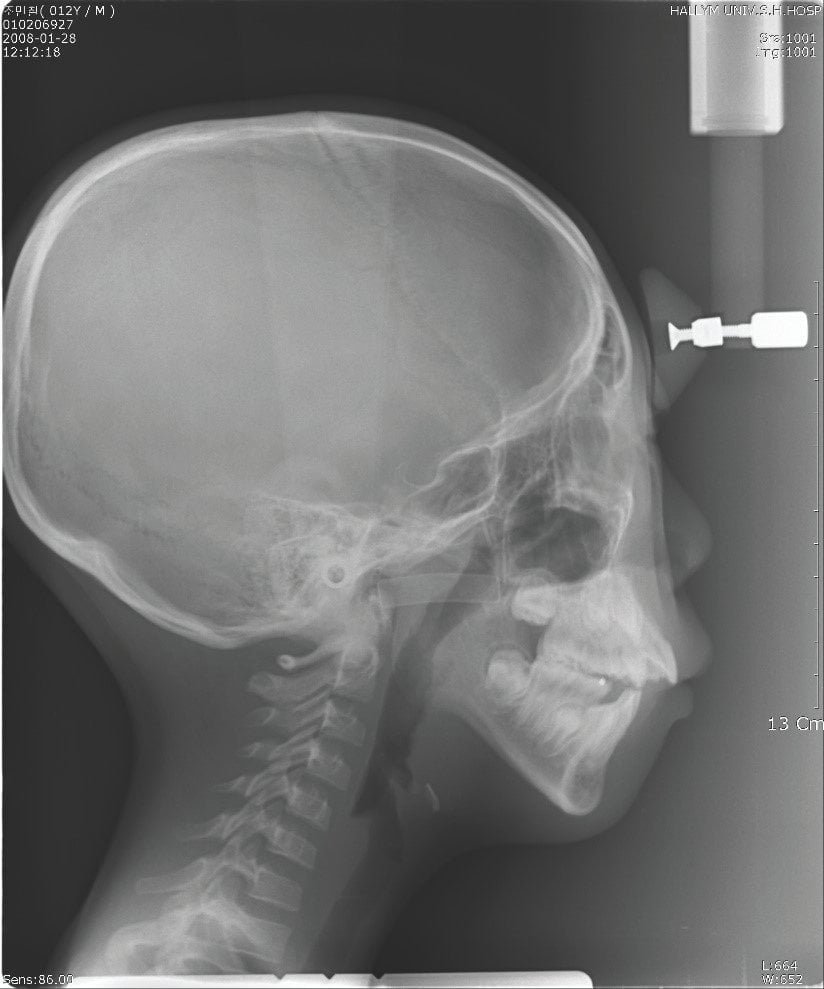

일단 턱이 작아 보이는 경우는 2가지의 경우가 있습니다. 첫번째는 아래턱은 정상인데 상대적으로 위턱이 나와서 아래턱이 작아 보이는 경우입니다. 두번째는 실제적으로 아래턱 자체가 작은 경우가 있습니다. 위의 두가지 경우 모두 II급 부정교합으로 분류되며 치료시기는 아이들의 최대 성장기입니다 <사진3>. 최대성장기는 한국 남자아이들 같은 경우 평균 만 10.5세이고 여자아이들의 경우는 평균 9세입니다. 최대성장기에 치료가 들어가는 이유는 치료기간을 짧게 그리고 효과적으로 하기 위함입니다. 아이들은 성장을 계속 하고 있기 때문에 발견 즉시 치료를 들어가면 더욱 효과가 좋을 수 있지만 전체 치료 기간은 길어질 수밖에 없으며, 비용도 많이 들고 또한 아이들도 지쳐서 동기부여가 안되기 때문에 최대성장기까지 기다렸다가 치료를 하는 것이 효율적입니다. 아이들마다 최대성장기는 다르기 때문에 정확한 최대성장기를 측정하기 위해서는 치과에 내원하셔서 X-ray 손목사진을 찍고 성장 판 분석을 해봐야 합니다.